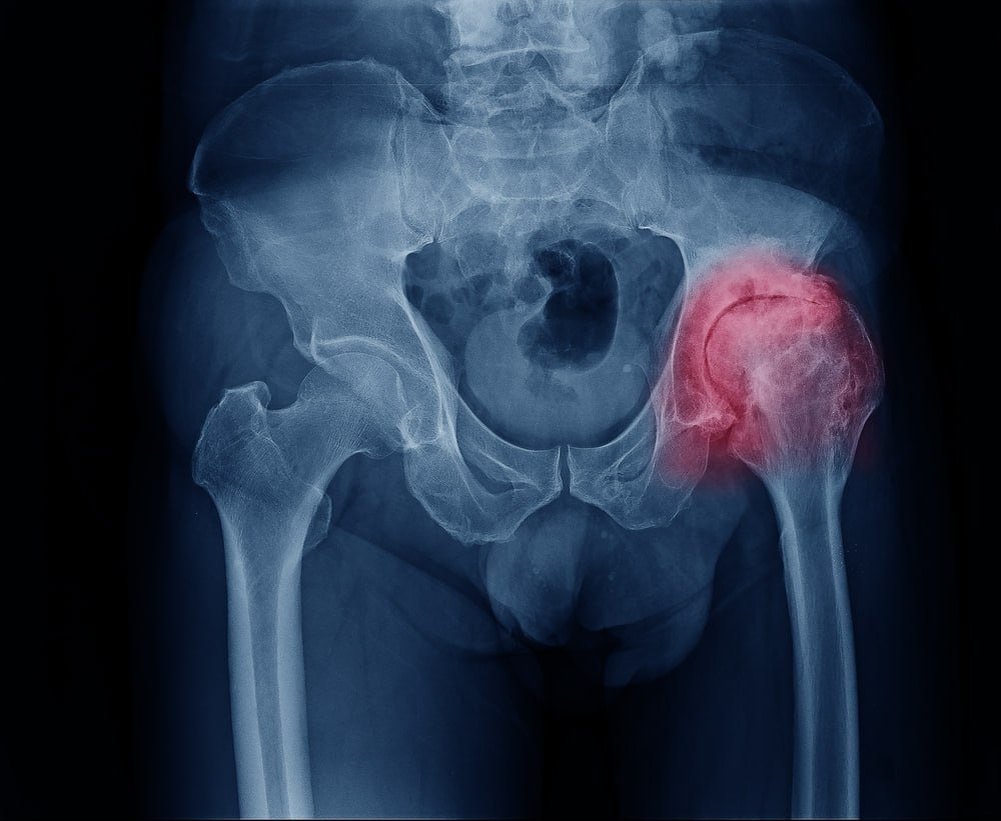

Тазобедренный сустав состоит из головки бедренной кости и вертлужной впадины, между которыми находится хрящ. При коксартрозе хрящ истончается и теряет упругость, что приводит к трению костей друг о друга, воспалению и боли. Болезнь развивается медленно: сначала дискомфорт появляется только после нагрузки, затем боль становится постоянной, а движения ограниченными. 🚶‍♂️💔